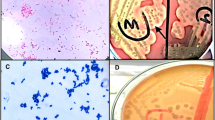

Cloxacillin has shown to reduce effects over bacterial biofilms from chronic infected animals. On the contrary, chitosan is a biopolymer with a wide range of antimicrobial properties30,31. Antimicrobial activity of chitosan was evaluated by flow cytometry and plate counts. Bacterial membrane integrity was analyzed using the SYTO9 dye that can be incorporated into all cells (both alive and dead) and propidium iodide (PI) dye that can only be incorporated into dead cells (Fig. 1A–C). We found that chitosan presented a strong antimicrobial activity not only on planktonic cultures (Fig. 1A,B,D), but also on preformed biofilms (Fig. 1C,D), in a dose-dependent manner. Chitosan concentration required for bacterial killing inside preformed biofilms was from 4 to 16 times higher than for the planktonic cultures of the same isolate (Fig. 1D). In our study, chitosan presented important bactericidal activity on CNS isolates from chronic bovine mastitis that was independent of the antibiotic resistance pattern.

Antimicrobial activity of chitosan against CNS isolated from chronic intramammary infections. CNS growth in planktonic and biofilms forms were treated with different concentration of chitosan. (A) Bacterial viability of planktonic cultures were analyzed by flow cytometry using SYTO9 and PI dyes. (B) Bar graph shows chitosan effect on planktonic growth of CM-CNS isolates by flow cytometry. (C) Bar graph shows chitosan effect on preformed biofilms of CM-CNS isolates by flow cytometry. (D) Data table represents MBC in planktonic and biofilms growth by plate count assay. These experiments were performed three independent times with three biological replicates and the data are represented by nine independent replicates. Data are shown as mean ± SEM. The p values were obtained using two-way ANOVA followed by Bonferroni post-hoc analysis. P values *< 0.05, **< 0.01 and ***< 0.001 were considered significant.